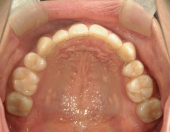

2年を少し過ぎたころには歯並びが良くなり、開咬もだいぶ改善されました。結婚式を予定していたため早期終了をさせていただきましたが、開咬が治ってハンバーガーをガブッと噛みきることができるようになって、とっても嬉しいです。式でもきれいな歯並びで、思いっきり笑うことができました。

出っ歯や八重歯などの歯並びの悪さばかりが気になっていましたが、開咬には前歯で物が噛みきれない、しゃべるときに息が漏れるなどの症状の他に、奥歯ばかりに負担がかかる為、歯の寿命を縮めてしまう可能性がありました。矯正で改善することができて本当によかっと思います。みなさんも歯並びで気になることがあったら、気軽に相談してみてくださいね。